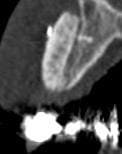

Je me permets de vous soumettre les clichés de scan à 5 mois d'une greffe d'apposition maxillaire antérieure secteur 11 12 que j'ai réalisée.

J'avoue avoir été surprise du hiatus qui existe encore entre greffon et os cortical initial, je suis d'ailleurs déçue je pensais que la forme que j'avais donnée permettait un meilleur "placage" du dit greffon.

D'après vous est ce que cette image est trop précoce dans le processus de cica et que mon "vide" va se combler dans les semainesà venir? je note bien l'intégration sur la crête et les bordures de la greffe.

ta 5 em coupe est pas si mal

sur la coupe 1 et 2 on percoit encore la corticale presqu'intact... on doit enclaver le bloc donneur dans l'os receveur

Il faut un contact intime du greffon avec le site receveur et ici cela ne devait pas être le cas sur toute la surface. Mais une partie semble bien minéralisée. Attends encore un mois avant d'intervenir, tu verras bien à ce moment là.

Je dois dire que quand j'ai reçu les images du scan j'ai fait défilé les coupes horizontales de cervical en apical et là j'étais ravie : on ne voyait cette maladaptation que dans une faible zone au tiers apical dans le creux de la concavité de 13. C'est après que j'ai déchanté.

Quand je fais circuler ma souris sur le logiciel de planification sur les zones "sombres" le logiciel m'indique une densité assez correcte très proche de celle de l'os spongieux du patient,du coup je me dis que la minéralisation est en cours....

Pourtant à partir de la coupe 142 on commence à voir une belle fusion entre les 2 surfaces.